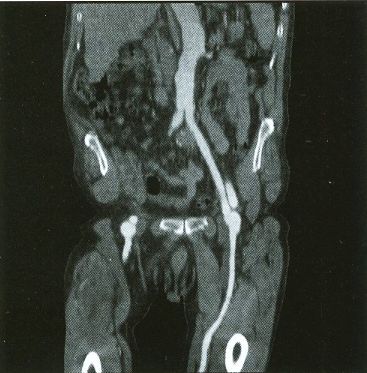

The following VS1 screen-shots were found in a binder along with the VPP photos and hundreds of 35 mm slides of all sorts of stuff:

Voxelscope I Screen Shots. First Row: Multiplanar Reformatting; Second Row: 3-D Shaded Surface

The annotation was generated by the software so no more cutting and pasting. :)

The pair of video monitors was the focus of the booth, displaying sequences of skulls and such from real CT datasets like those in the above photos being rotated, sliced, and diced at reasonably rapid update rates. The instructions for performing the operations were captured and recorded but the actual voxel processing was done in real-time based on the stored program. Thus, no one needed to be constantly spinning the trackball, though that could have been arranged upon request. :) The monitors were up high so visitors couldn't get close enough to see how poor the resolution was. :( :) It is believed that VS1 had a microcode-based pipeline running at 10 MHz so that a 128-cube (2,097,152 voxels) could be manipulated at around 5 images per second. The display was 256x256 pixels on a 60 Hz non-interlaced display - double that of VPP. But object space could be configured to be any arbitrary rectangular prism as long as all the data fit into the voxel processor's memory. The photos, above, are typical of the displays at RSNA.